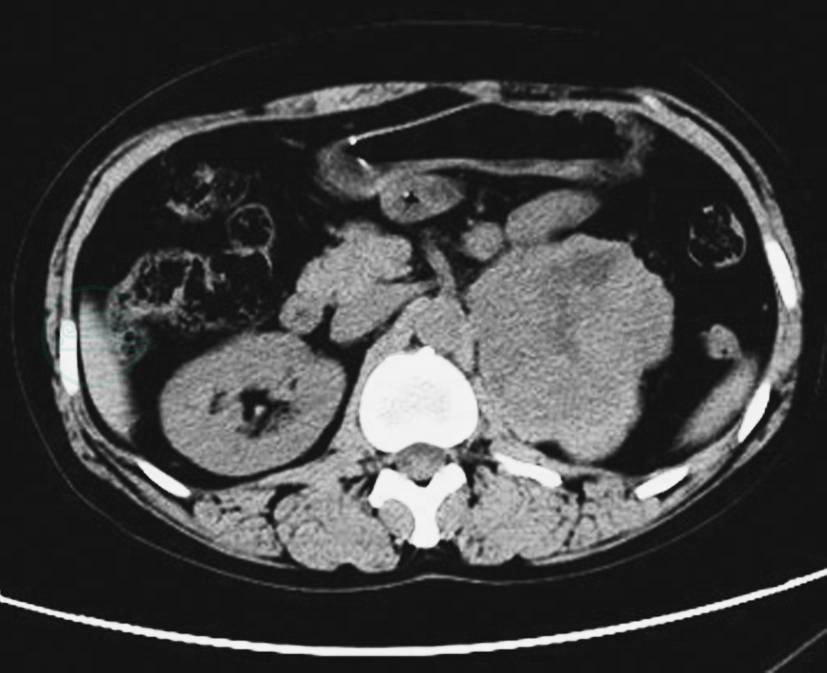

图6左侧肾上腺恶性嗜铬细胞瘤

CT静脉期示左侧肾上腺瘤体,形态不规则,囊变坏死明显,瘤体侵犯肾脏、脾脏及膈肌脚等周围结构